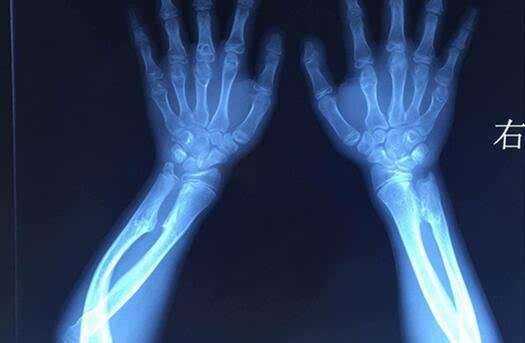

骨科医生需要从点开始学习,也就是一根根一块块的骨头,每块骨头结构特点,长短,粗细,角度,哪里有个凸起,哪里有个凹陷,哪里宽哪里窄,哪里有斜坡,力线如何,这些都是要研究清楚的,还要理解为什么每块骨头都有这些不同,什么作用?周围有那些肌肉附着,神经血管经过,肌肉神经血管的走向,如何拐弯,为何要这样?神经血管和肌肉骨骼的相互之间的关系,如果这些结构的某个位置损伤病变了会出现那些异常情况!每个关节都有类似的情况!这也就是从点到线到面的的思维了!